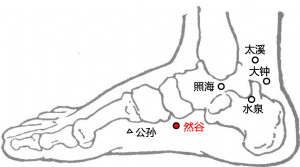

然谷爲經穴名(Rángǔ KI2)[3]。出《黃帝內經靈樞·本輸》。別名龍淵、然骨[4]。屬足少陰腎經[4]。然谷是足少陰腎經的滎穴,五行屬火[4][5]。此穴在舟骨之下,舟骨古稱然骨,故名然谷[5]。然谷穴主治婦科、前陰、脾胃等疾患:如月經不調,陰挺陰癢,痛經,白帶,血崩,不孕,遺精白濁,小便淋瀝,疝氣,黃疸,消渴,泄瀉,頭痛,喉痹,厥心痛,咳喘,咯血,胸滿,腰脊痛,癲疾,臍風,腳氣,腳腿轉筋,瘡疥癬癢,咳血,陰癢,陰挺,陽痿,遺精,臍風口噤,足跗腫痛,帶下,咽喉腫痛,口噤,小便不利,小兒臍風,胸脅脹痛,口噤不開,下肢痿痹,足跗痛,現代又多用然谷穴治療咽喉炎,扁桃體炎,尿道炎,睾丸炎,精液缺乏,糖尿病,陰部瘙癢,心肌炎,破傷風,足部扭挫傷,膀胱炎,遺尿,不孕症,精神病等。

然,通燃,《說文》:“燒也,從火,然聲。”谷,泉出通川曰谷,空虛不有亦爲谷。舟骨粗隆,古稱然骨。《子午流注說難》說:“然谷乃腎所溜之滎穴,陰滎爲火穴,坎中有一陽無根之少火能生氣。”其穴亦名龍淵,爲足少陰腎脈之溜,五行屬火,別名龍淵,潛龍在淵之義也,其性似龍雷之火出於淵也。男女精溢,不孕者皆取之,此火能然(燃)於深谷之中,不受水克。養生家謂水中有真火,今學者謂地心有真熱。觀本穴所治,凡腎火衰微所生種種弱症,刺此穴俾以發動內熱也,故名之。足內踝前下高起之骨,古稱然谷,是穴正當然骨下緣。《黃帝內經靈樞·本輸》載:“然谷,然骨之下者也。”《鍼灸甲乙經》:“在足內踝前起大骨下陷中。”以骨名其穴,因名然谷。[6]

足部[7]

然谷穴下爲皮膚、皮下組織、展肌、長屈肌。有足底內側及跗內側動脈分支。分佈着小腿內側皮神經末支及足底內側神經。皮膚由隱神經的小腿內側皮支分佈。該處爲足底與足背皮膚移行部位。展肌由足底內側神經支配,長屈肌由脛神經的肌支支配。